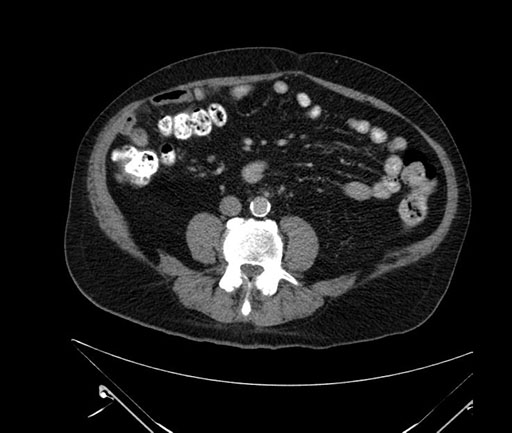

Axial - stented